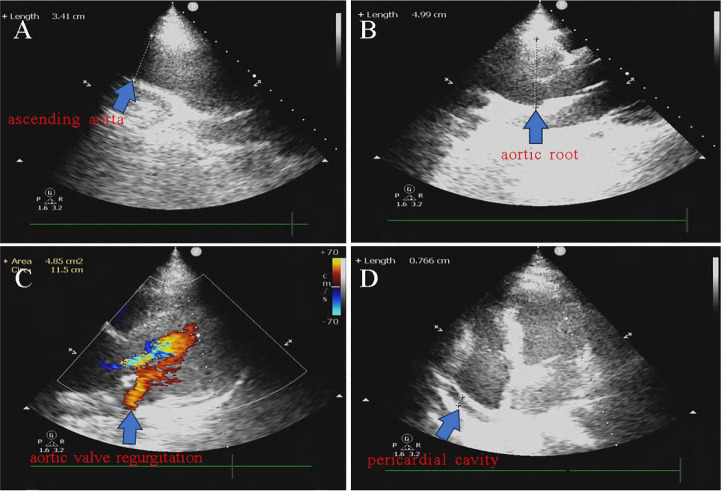

Pregnancy-related aortic dissection is an uncommon and serious condition since it poses a risk to the lives of both the mother and the fetus. Here, we describe a pregnant woman who suffered from aortic dissection twice during the same pregnancy and whose fetus was safely delivered following aortic root replacement and thoracic aortic stent-graft implantation.